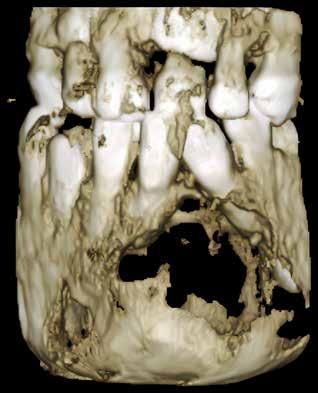

Patienttilfælde 1 (Fig. 1) er en 37-årig kvinde, henvist efter succesfuld behandling af stadie 3-parodontitis. Der er nu sundt

Før behandling

parodontium, ingen pocher over 4 mm, og både blødnings- og plakindeks er under 10 %. Patienten er motiveret for ortodontisk behandling, da hendes tænder er vandret over tid, delvist som følge af reduceret parodontium.

Der ses anterior trangstilling i begge kæber og overerupterede 1+1 og 2,1-1,2, hvilket resulterer i dybt bid med 2- tæt på ganepåbidning. Der er normale sidetandsrelationer, men der ses 5 mm horisontalt overbid (HOB) og 7 mm vertikalt

overbid (VOB). Papillen mellem 1+1 er betydeligt reduceret pga. fæstetab, og de mesialt kippede 1+1 har resulteret i en ”dark triangle”. Den facioorale funktion er for nuværende i.a. Panoramarøntgen (Fig. 1, I) viser marginalt knogletab i begge kæber og fravær af 8,7+7,8 og 8,7-8.